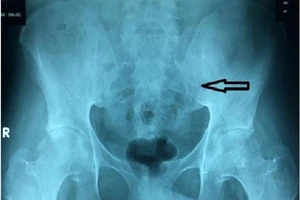

Suýt cứng khớp tay chân do nằm bất động 6 tháng trị cột sống